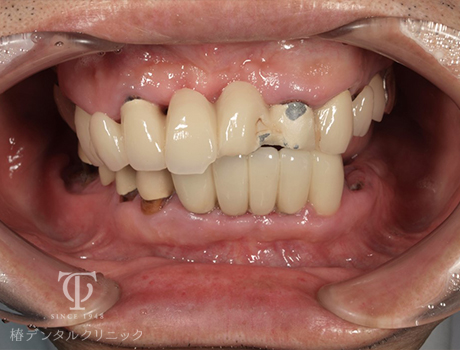

術前

-

- 症状

- 右上の痛み

- 治療期間

- 約1年半

- 治療費用

- (上顎)インプラント治療:473,000円×2

(上顎)AGCテレスコープ義歯:1,500,000円

(下顎)インプラント治療:473,000円×2

右上の歯が痛いということで来院されました。インプラントとAGCテレスコープという方法でかみ合わせを再構築しました。

【リスク・副作用】

インプラント治療後、痛みや違和感、出血、腫れなどが出る事があります。喫煙者、糖尿病などの方の場合、歯が生着しない場合があります。入れ歯を清潔に保たないと虫歯や歯肉炎、歯周病になるリスクがあります。